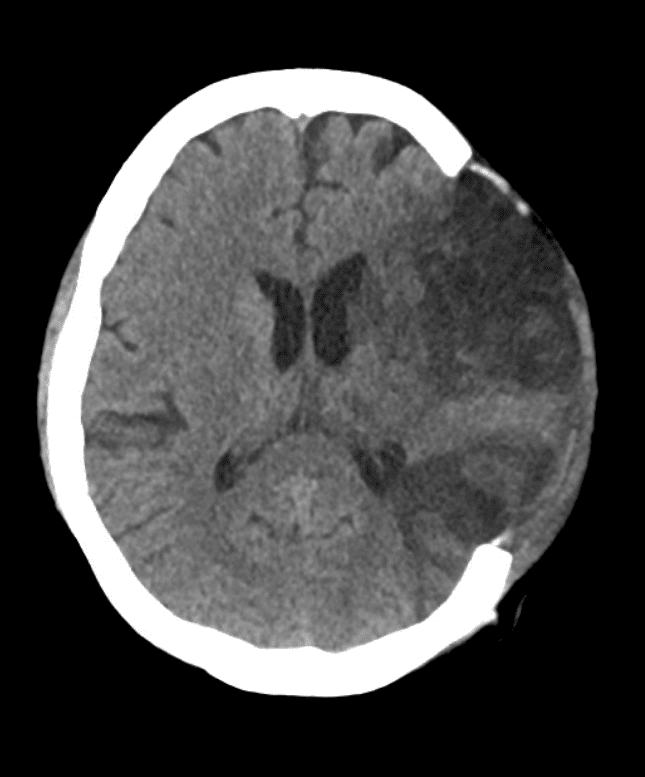

Immagini post operatorie